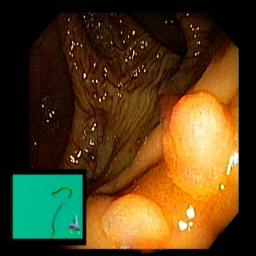

The performance metrics for Edgeconnect and AOTGAN on the validation data after fine-tuning the models, are shown in Table II. In addition to qualitative evaluation, Figure 3 provides example data from the different steps of the PolypConnect pipeline using the EdgeConnect model and the AOTGAN model. Due to obvious visual differences in the generated polyps between the models, we selected the EdgeConnect model as the main polyp inpainting model of the PolypConnect pipeline for further evaluation and qualitative assessment by domain experts.

Figure 3: Sample data used and generated in the different steps of PolypConnect pipeline. (a) - real polyp images, (b) - manually annotated polyp masks, (c) - randomly selected colon images used as input to the final step of PolypConnect, (d) - extracted edge images of row c. (e) - extracted edge images of polyp regions of row a using the masks of row b. (f) - combined edge images of row d and f. (g) - generated polyp on the images of row c using EdgeConnect. (h) - generated samples from AOTGAN.